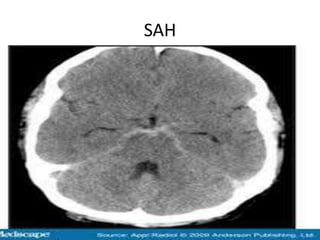

SAH

Vascular Insults • SubarachniodHemorrhage. • Lobar and basal ganglia bleeds. • Ischemic strokes. • Venous infarcts. • Disections